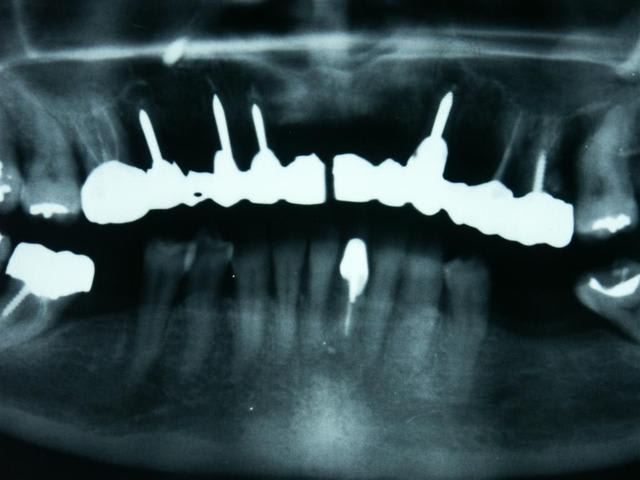

ba moi, je fais des implants intra-radiculaires, de marque casto-spline, tu connais ?